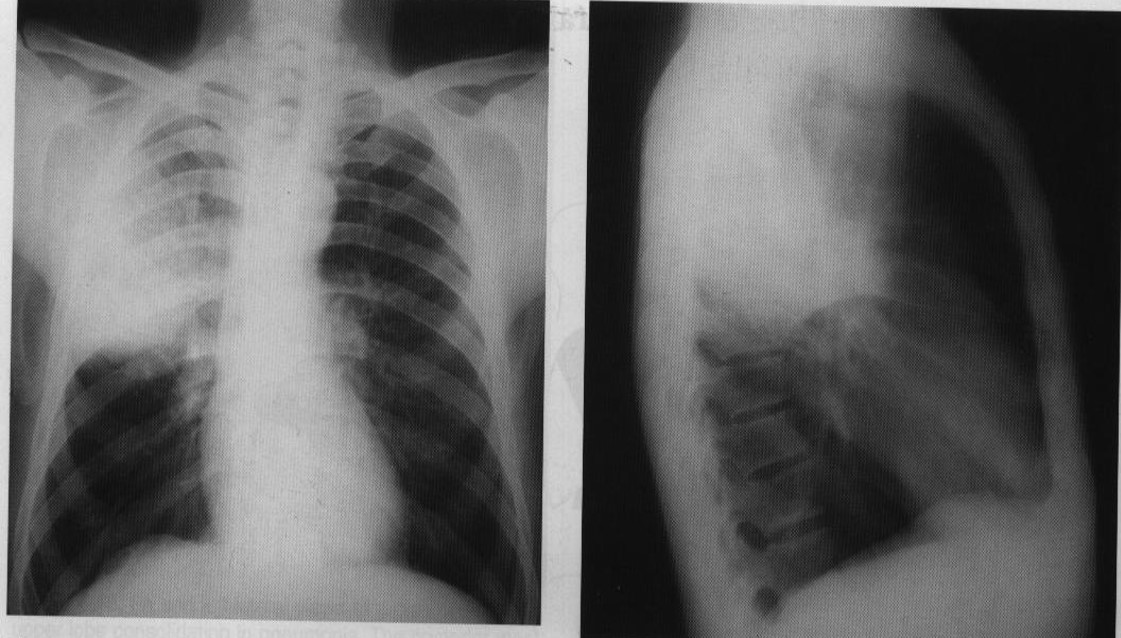

7 year old previously healthy Hispanic male presented to an emergency department with 1 week of a non-productive cough and intermittent fevers measured at home to 103.5°F

View:

DX:

View: PA/lateral

DX: pneumonia